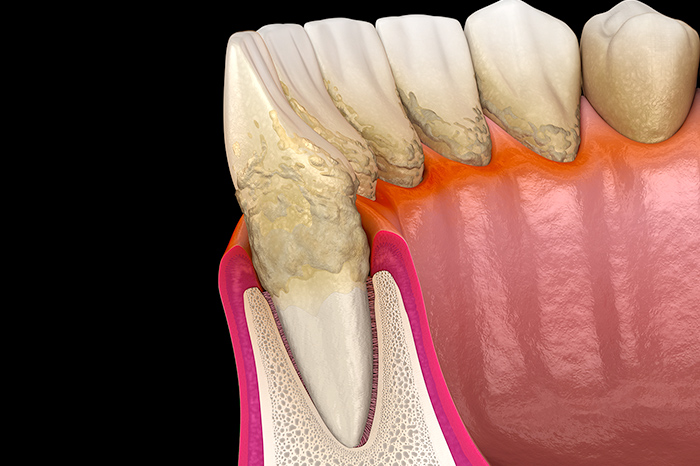

歯ぐきや歯槽骨など歯を支える歯周組織に炎症が生じて、出血する、骨が減るなどの症状が出ることを歯周病と言います。初期段階ではほぼ自覚症状がなく、進行してようやく気付くケースが多いのが歯周病の特徴です。放置すれば歯を失う原因になりますので、異変を感じた際はお早めに当院までご相談ください。

歯石の蓄積は歯周病菌などの細菌を増殖させて、歯科疾患の原因となります。そのため、スケーラーという専用の器具を使用して、歯に付着した歯石を取り除きます。基本的な歯周病治療の一種です。

SRP

スケーリング、ルートプレーニングの略からSRPと呼ばれており、歯周病治療の一環として行われます。歯の表面や根元に付着した歯石を徹底的に取り除くとともに、歯垢やバイオフィルムの再付着を防ぐ効果も期待できます。